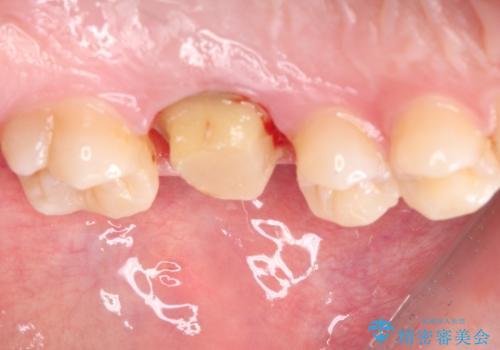

- 矯正治療後に目立つ銀歯を白くしたいとのことで来院された患者様です。

右下の銀の詰め物は、外してむし歯を除去した後、セラミックインレーにて修復することとしました。

左上の銀歯は、銀歯の下に金属の土台が入っているため、その土台を除去し、ファイバーコアにやり替えて、オールセラミッククラウンにて補綴することとしました。